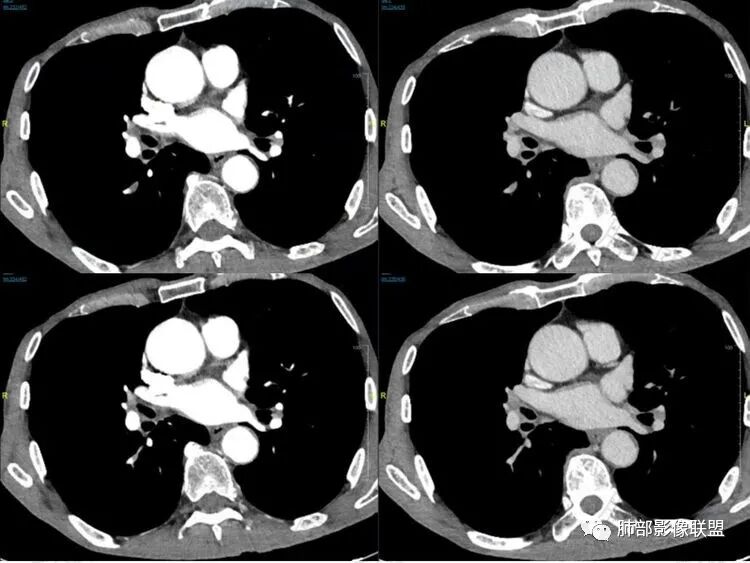

1鸭蹼状突起、腊肠样尾巴、指状突起、蠕虫、分支及条状

因为病灶沿支气管粘膜下及周围血管生长,走形方向与支气管一致,所以支气管血管周围生长也是SCLC的典型征象。当然有时会像小山丘或者灌汤包一样趴在肺边缘。

2娘小崽大、淋巴及血行转移早、冰冻纵隔及肺门、血管脂肪间隙消失

因为病灶侵袭力强,病灶易沿淋巴道、间质及心血管间隙等结构侵犯并密切挤压上述结构,常常能够观察到脂肪间隙消失。易于出现冰冻纵隔。原发灶与肺门转移灶可形成哑铃状外观,甚至转移灶体积大于周围原发灶,有人称之为“娘小崽大”。早期病灶有时很小甚或隐匿,仅能看到转移灶,或转移淋巴结与原发灶融合分界不清。病变向肺门延续的串珠样淋巴结转移也是SCLC的典型特点。

3

血管包埋征

病灶侵袭力强大,早期沿粘膜下疏松结缔组织及血管旁间隙扩散,包绕血管,血管会受压变形,因为小细胞癌破坏力弱,血管没有被破坏,所以仅仅表现为包埋浸润,但血流面光滑。

4

乏血供,沼泽样坏死

、罕见空洞

病灶肿瘤密集而供血血管相对不多,密度较均匀,轻度强化,呈乏血供,有时候可以坏死,坏死不彻底,坏死区分散而较小,呈沼泽样坏死,很难造成引流支气管的破坏,所以空洞罕见。

5

阻塞性炎症轻,阻塞性肺不张少见

支气管内肿瘤大多来自淋巴结转移,而且侵入支气管管壁的SCLC组织喜欢沿粘膜下组织间隙浸润,支气管粘膜面保留,所以支气管大多数表现为狭长而非填塞或截断,所以阻塞性炎症轻,阻塞性肺不张罕见。

6边缘圆钝、光整,未见毛刺

神经内分泌肿瘤边缘通常圆钝,而且SCLC或周围没有任何促纤维结缔组织反应,质地软,所以边缘圆钝、没有毛刺。